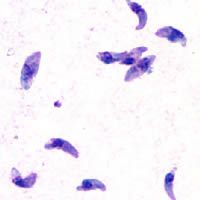

弓形虫(图片来源:medicalxpress)

刚地弓形虫(图片来源:维基百科)

弓形虫的形态,从左往右:速殖子、速殖子超微结构、包囊(图片来源:jotscroll)